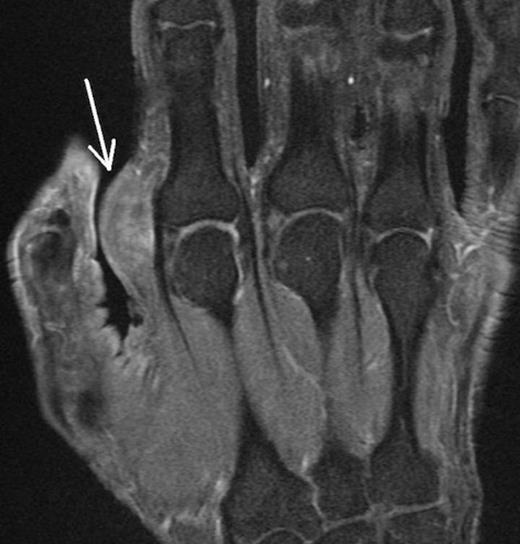

Coronal Fat Suppressed Image of the mass – Depicted by the white arrow

Ultrasound scan prior to referral suggested a complex mass with solid and cystic components. MRI scan demonstrated (Figure 1 and 2) the mass to be mixed fibrous and cystic components reported by a radiologist to be either fibromatosis or a desmoid tumour. The lesion was closely positioned to the Metacarpophalangeal joint but not invading the capsule. There was no sign of osteoarthritis of the joint. A marginal excisional biopsy was performed utilizing a Bruner incision. A firm fibrous mass was found with pale coloured tissue with cystic spaces containing ganglion like jelly. The mass easily reflected off the subcutaneous dermis but deep was intimately related to the palmar fascia. The radial digital nerve and vessels were separate to the mass and preserved. The wound healed well without complication. Histopathological analysis showed an irregular mass of fibrous tissue and pale mucoid material measuring 34 x 25 x 15 mm. There were multiple cystic areas containing mucoid material. (Figure 3)